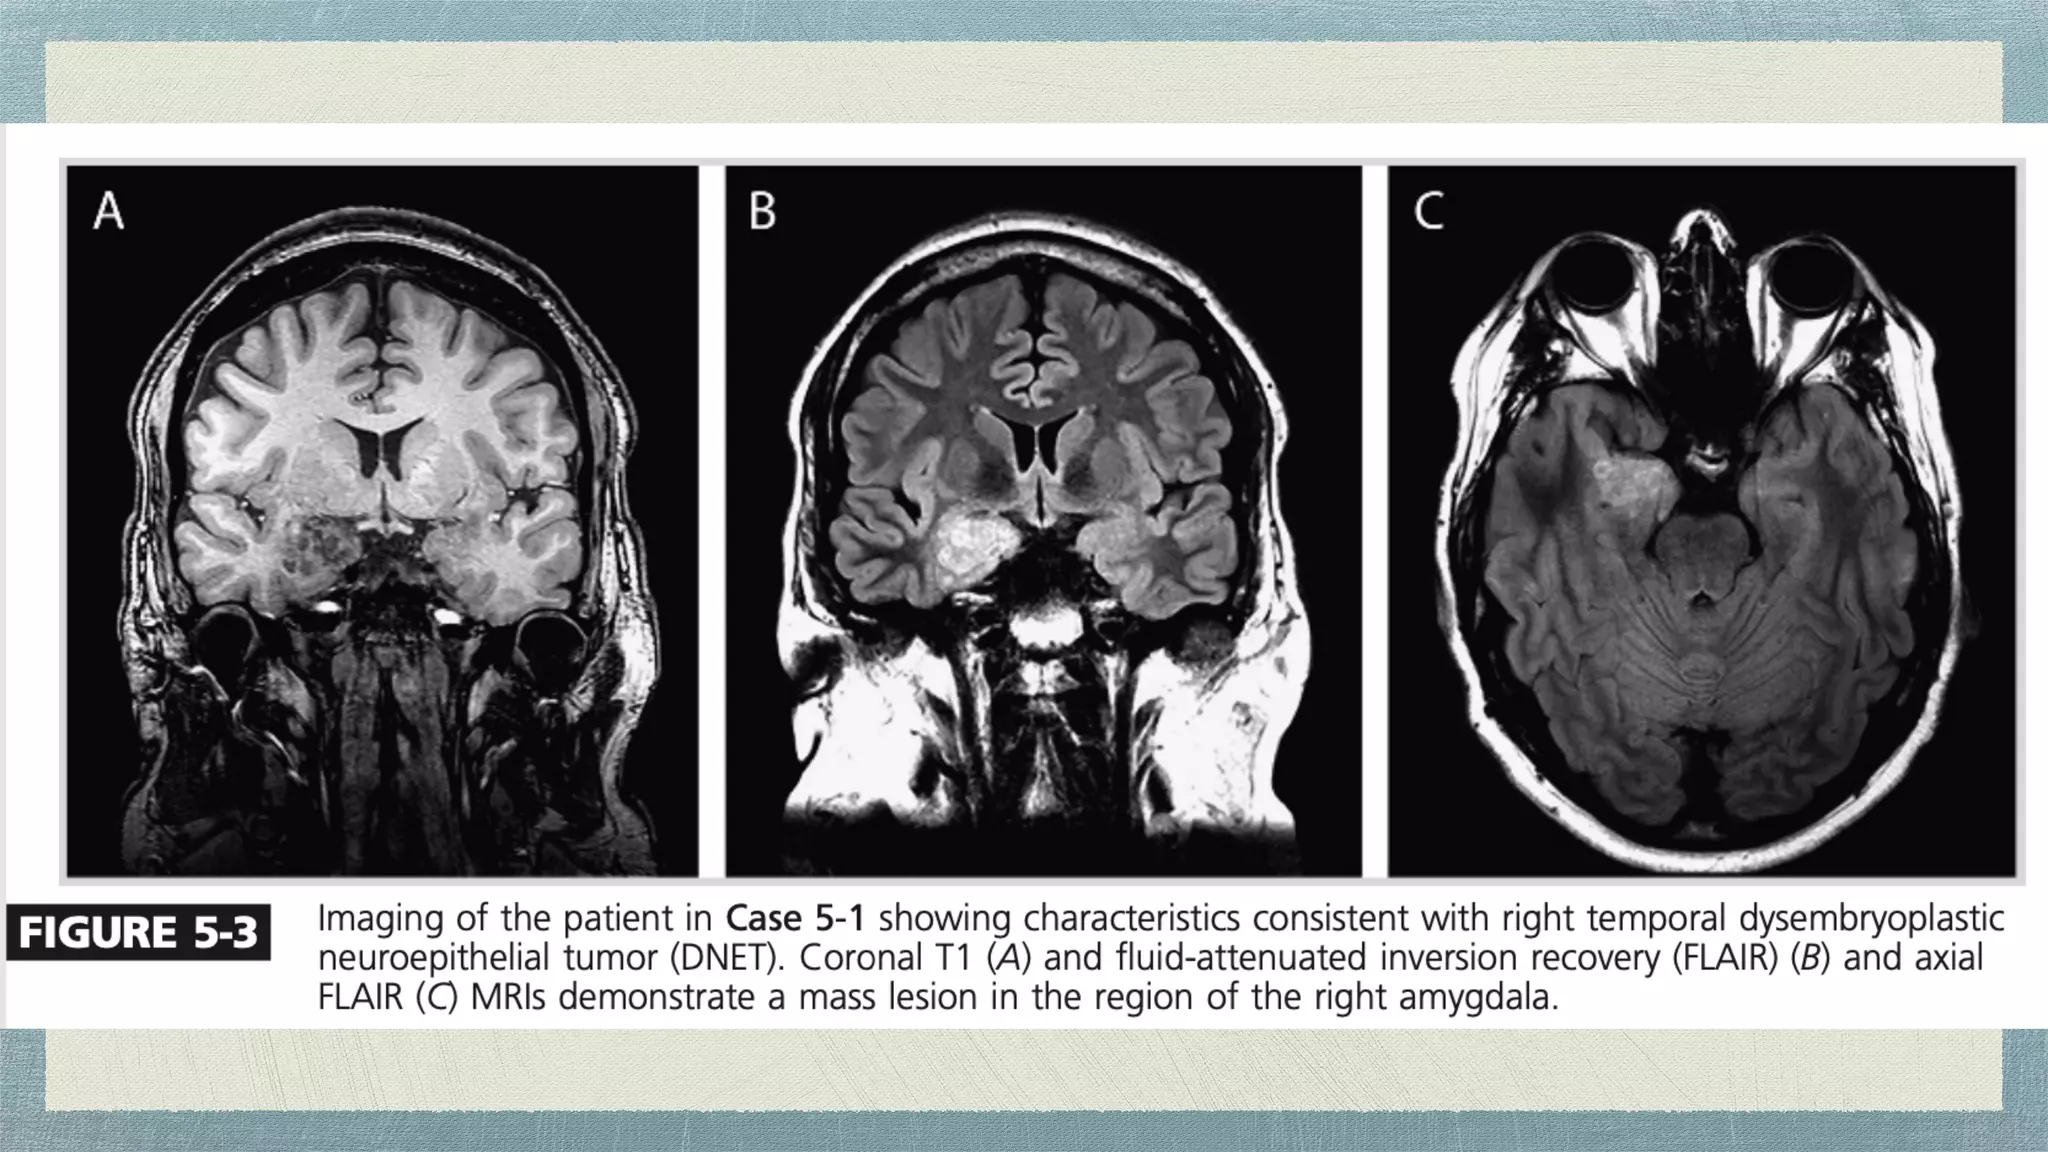

An MRI of the brain without contrast is recommended in the evaluation

of a patient with suspected mesial temporal lobe epilepsy

An enhanced MRI may be used dependent on local imaging protocols and

suspected etiologies.

It is preferable to include coronal T1- and T2-weighted images with thin

cuts (less than 3 mm) through the temporal lobes to properly evaluate the

hippocampus.

Imaging

Key imaging characteristics to evaluate for hippocampal

sclerosis are asymmetric size (smaller on the affected side) and

increased T2 signal in the hippocampus consistent with gliosis.

Imaging An MRI ofthe brain without contrast is recommended in the evaluation of a patient with suspected mesial temporal lobe epilepsy . An enhanced MRI may be used dependent on local imaging protocols and suspected etiologies. It is preferable to include coronal T1- and T2-weighted images with thin cuts (less than 3 mm) through the temporal lobes to properly evaluate the hippocampus.

• 26.

Imaging Key imaging characteristicsto evaluate for hippocampal sclerosis are asymmetric size (smaller on the affected side) and increased T2 signal in the hippocampus consistent with gliosis. Inclusion of gradient echo imaging may assist in the identi fi cation of vascular etiologies